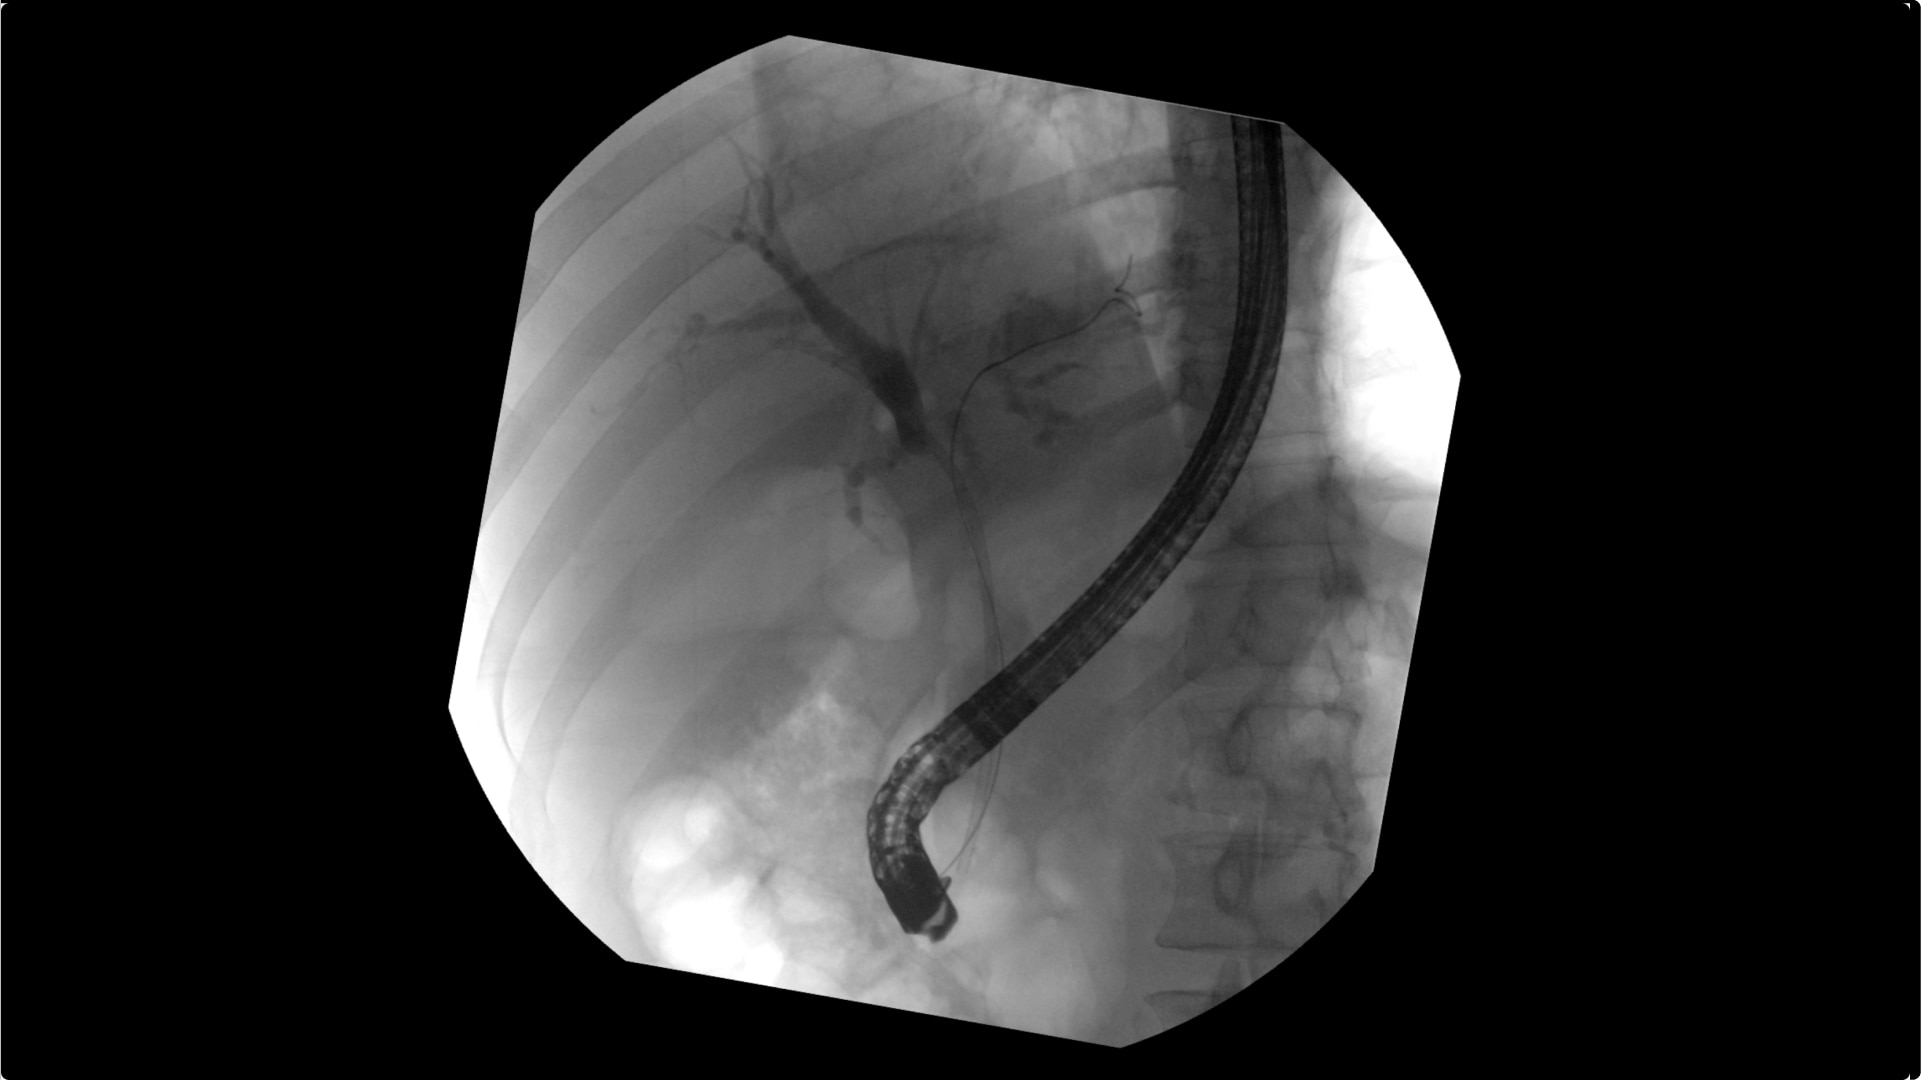

Clearly visualize the GI tract of patients, regardless of size, during a wide range of endoscopic procedures, including ERCP. OEC C-arms offer amazing image quality at low dose and provide enhancements for clear visualization during movement in soft tissue, such as during guidance of low-density drainage tubes or thin biopsy brushes. A large, clear display with comfortable viewing enables effortless workflow.

See detail 1 for 1 from detector to a 4K UHD display for stunning image quality and visualization of low density drainage tubes and thin biopsy brushes.

With OEC Elite CFD, the General HD preset profile optimizes to present high contrast, enhanced edge images to optimally see small detail such as stones in pancreatic duct.

Live Zoom up to 4X during a fluoro or Cine without the additional dose of Mag modes or resulting X-ray tube heat buildup to see guidewires or tubes during procedures.

Capture up to 22% more Field of View by positioning the OEC Elite detector closer to patient anatomy with the OEC low-profile X-ray tube housing compared to mono-block C-arms.